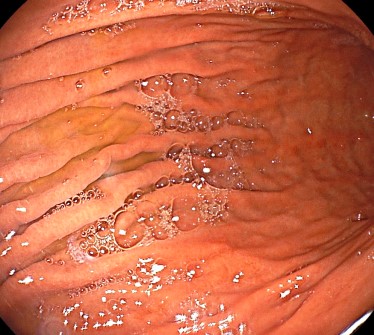

La gastritis es la inflamación del revestimiento del estómago. Puede ser aguda, que es de corta duración, o crónica, cuando persiste durante un período prolongado. La causa más común de gastritis es una infección bacteriana por Helicobacter pylori, aunque también puede ser causada por el uso excesivo de medicamentos antiinflamatorios no esteroideos (AINEs), consumo excesivo de alcohol, estrés, fumar, trastornos autoinmunes u otras enfermedades.